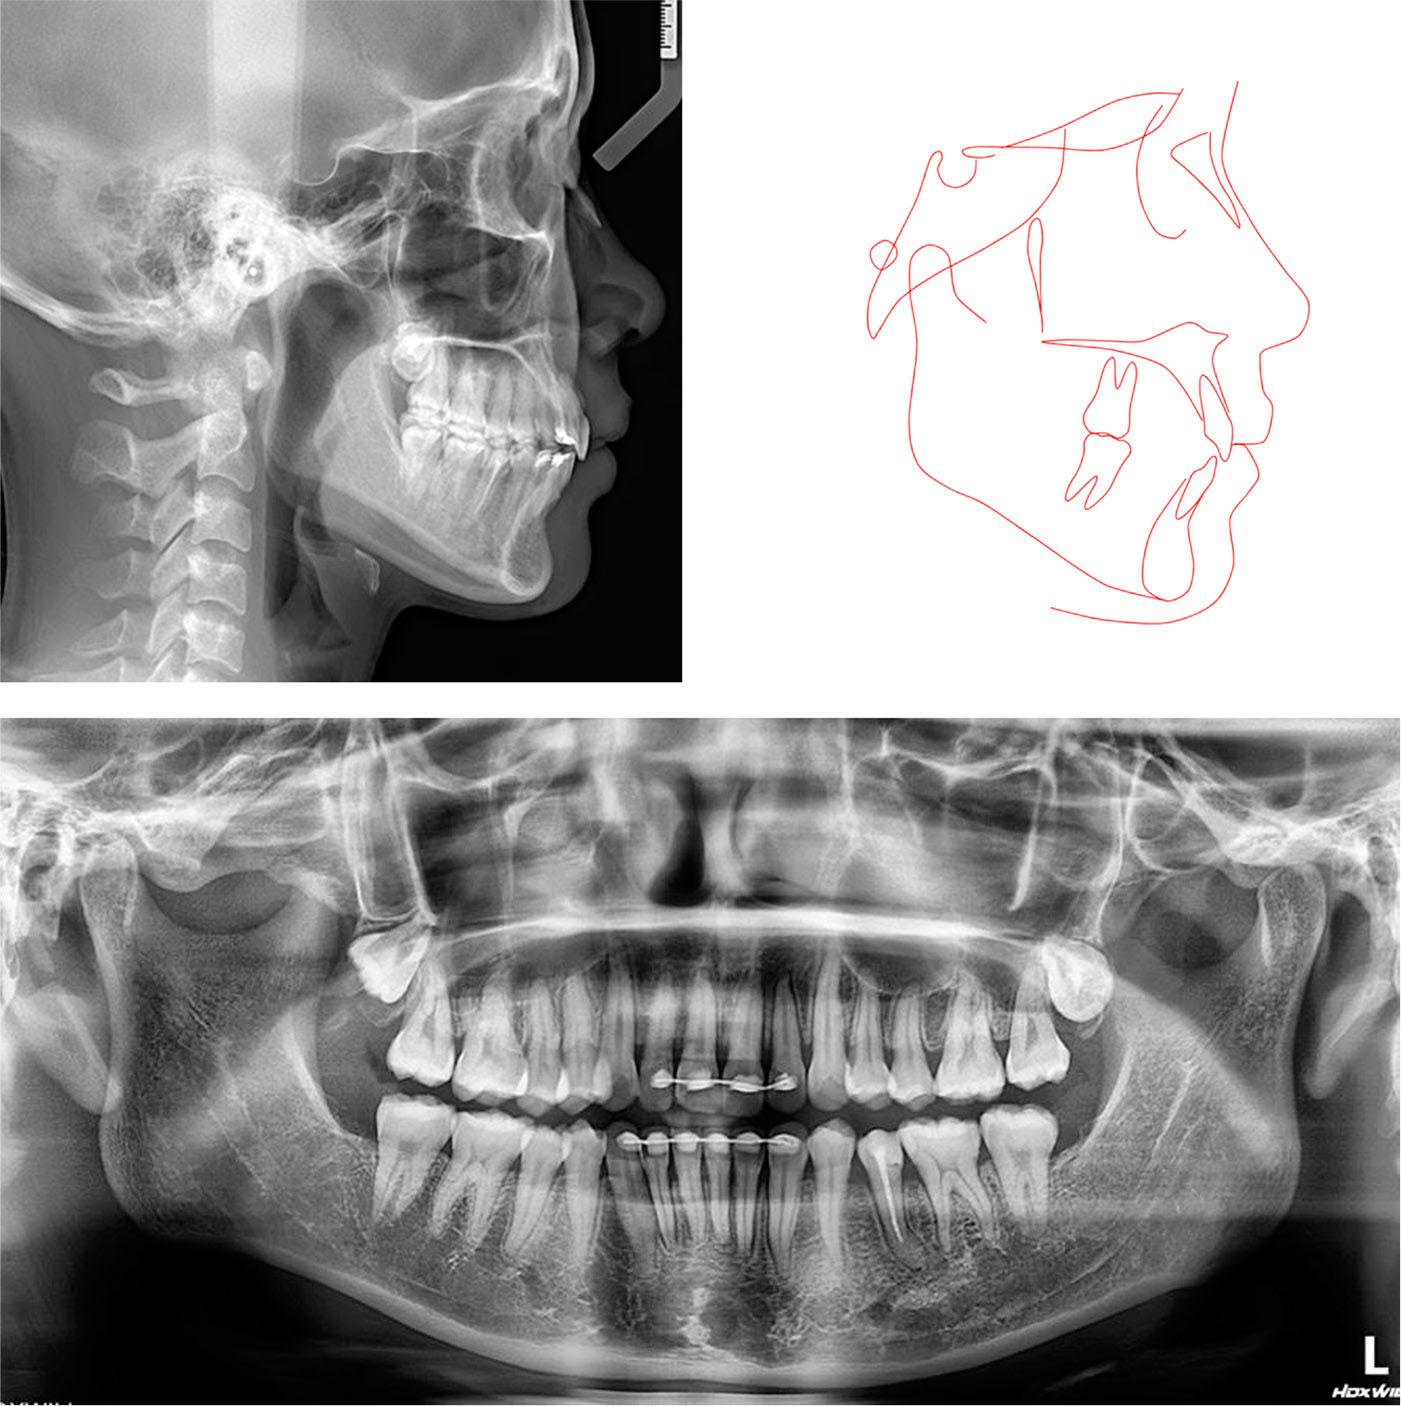

Figure 4.